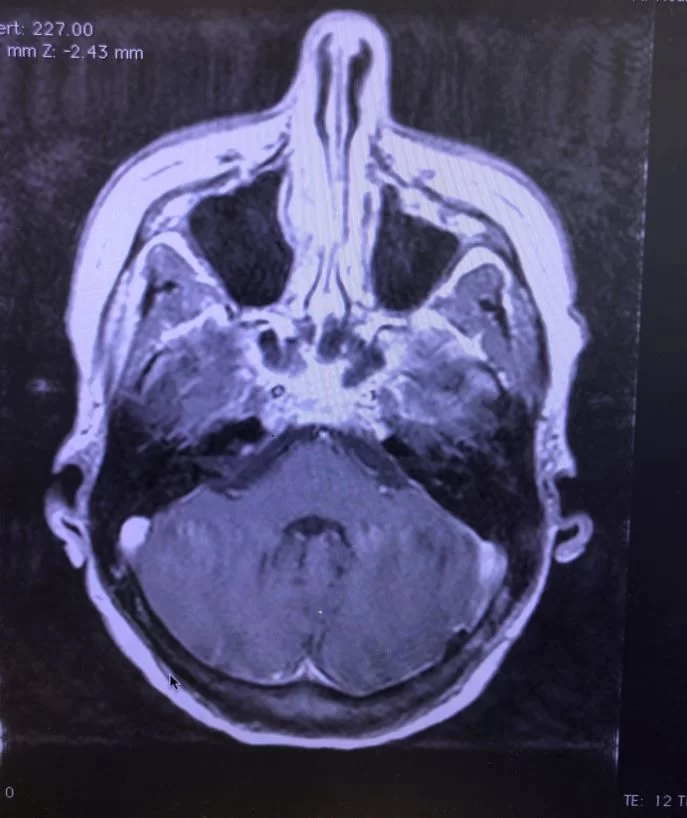

Ο προεγχειρητικός έλεγχος ανέδειξε μηνιγγίωμα της κρανιοαυχενικής συμβολής με εγκολεασμό σημαντικών αγγειακών και νευρικών δομών και επέκταση προς την αντίθετη πλευρά.

Η μετεγχειρητική μαγνητική τομογραφία εγκεφάλου δείχνει ένα εξαιρετικό αποτέλεσμα, με πλήρη αφαίρεση της βλάβης. Η ιστολογική εξέταση επιβεβαίωσε τη διάγνωση (μηνιγγίωμα WHO I).

Πρόκειται για ένα εξαιρετικά απαιτητικό χειρουργείο λόγω της θέσης του όγκου. Παρόλο που πρόκειται για μια καλοήθη βλάβη (μηνιγγίωμα), ο όγκος αναπτύσσεται στο ύψος του ινιακού τρήματος και εγκολεάζει πολύ σημαντικές νευραγγειακές δομές. Επιπλέον, η μορφολογία του όγκου είναι εξαιρετικά σύνθετη, μια και επεκτείνεται έμπροσθεν του στελέχους του εγκεφάλου στην απέναντι (δεξιά) μεριά.